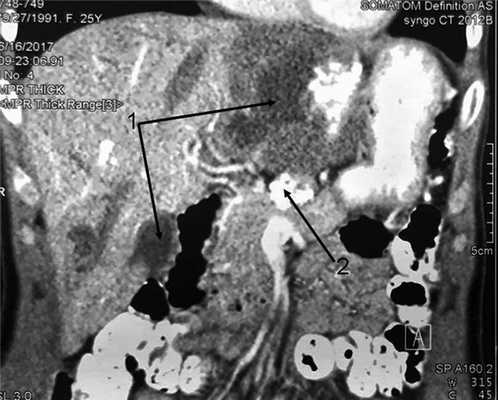

При поступлении общее состояние удовлетворительное, сознание ясное, кожный покров и видимые слизистые оболочки бледно-розовые, обычной влажности. Аускультативно дыхание в легких везикулярное, проводится во все отделы, хрипов нет. Язык влажный. Живот асимметричный из-за объемного образования, занимающего область правого подреберья и эпигастрия. При пальпации образование плотной консистенции, бугристое, безболезненное, малоподвижное. В общем анализе крови повышенная СОЭ — 23 мм/ч, других изменений, в том числе эозинофилии, нет. Биохимические показатели крови в пределах нормы. Уровень антител к антигенам гельминтов (эхинококк) в 4 раза превышает допустимые показатели (коэффициент позитивности 3,37 при норме менее 0,9). Для оценки ангиоархитектоники печени, а также для уточнения локализации объемного образования относительно магистральных сосудов и желчевыводящих путей пациентке выполнены МСКТ и МРТ. МСКТ: печень с ровными контурами, умеренно увеличена в размерах, косой вертикальный размер 18 см, в левой доле визуализируется объемное образование неправильной формы размером 84×105 мм с кальцинатом 33,5×40 мм. В артериальную фазу не накапливает контрастное вещество, в венозную и паренхиматозную фазы сохраняет низкие денситометрические показатели и приобретает четкие бугристые контуры за счет контрастирования окружающей паренхимы печени. В SVI сегменте визуализируется образование низкой плотности (15—11 ед. Н), неправильно округлой формы размером 26×30 мм, не накапливает контрастное вещество во все фазы исследования. На остальных участках паренхима печени однородной структуры до (56 ед. Н). Внутри- и внепеченочные желчные протоки не расширены. Над телом железы визуализируется кальцинат размером 20 мм (рис. 1). Рис. 1. МСКТ-грамма брюшной полости. Патологические образования в печени (1), поджелудочной железе (2).